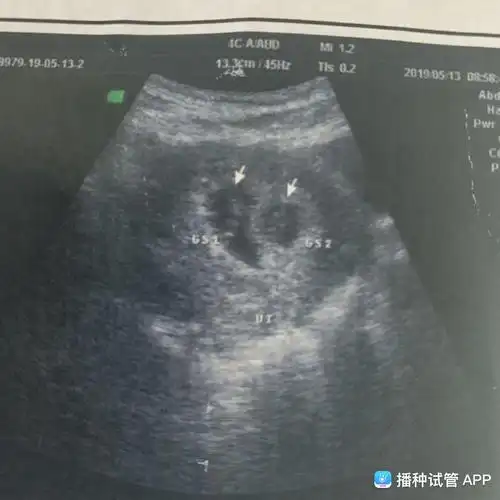

昨天查孕囊是双胞胎5周,我新手妈妈第一胎,有经验的姐妹进来聊聊.

真的是双孕囊啦

[试管婴儿]双胞胎这个孕囊大小差别好大,隔